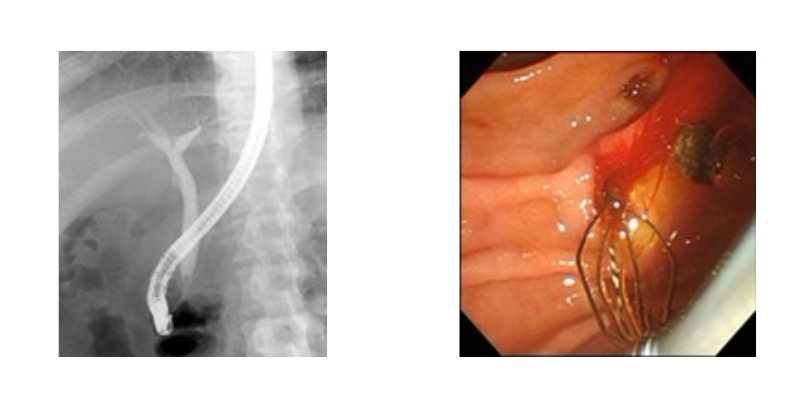

ERCP検査(内視鏡的逆行性胆道膵管造影)

口から内視鏡を入れ、胆管や膵管にカテーテルを挿入し、造影剤を使用して胆管・膵管の異常を調べる検査です。検査に続いて胆汁や膵液を外に排出させる治療(ドレナージ治療)を行うことがあります。X線を連続的に照射し、リアルタイムで状態を確認しながら治療を行います。